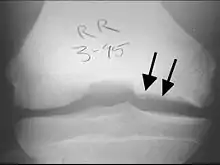

X-rays show lucency of the ossification on the anterior aspect of the knee in juvenile patients. In older people, the lesion typically appears as an area of osteosclerotic bone with a radiolucent line between the osteochondral defect and the epiphysis. The visibility of the lesion depends on its location and on the amount of knee flexion used. Harding described the lateral X-ray as a method to identify the site of an OCD lesion.[36]

Sagittal MRI: Linear low T1 signal at the articular surfaces of the lateral aspects of the medial condyle of the femur confirms the presence of OCD.